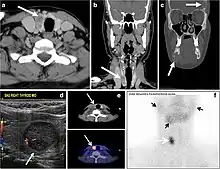

Fig. 22. A 26-year-old male patient with elevated serum parathyroid hormones and calcium secondary to intra-thyroid parathyroid adenoma. a, b Enhanced axial and coronal CT scan of the neck demonstrate a well-defined hypodense right thyroid nodule (white arrows). c Bone window coronal CT scan shows lytic expansile lesions at the right mandible and left frontal bone (white arrows). d Transverse colour Doppler ultrasound of the neck demonstrates a well-defined, heterogonous, predominantly hypoechoic right thyroid nodule measuring 2.7 cm, with mild increased vascularity and no internal micro-calcifications (white arrow). e, f Delayed anterior planar and fused SPECT/CT parathyroid Sestamibi scan at 2 hours demonstrate persistent focal activity in the right thyroid lobe (white arrows). Note the scattered mandibular/maxillary uptakes in planar image representing the known brown tumours.[1]